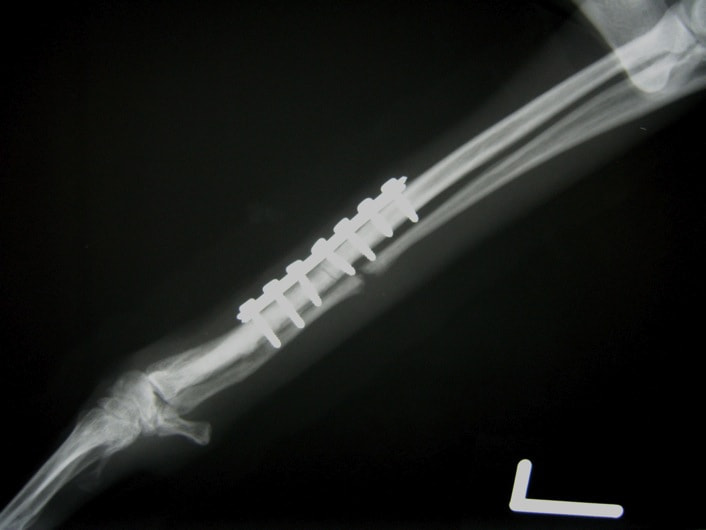

トイプードル 右遠位橈尺骨短斜骨折のALPSによる内固定

当院ではAdvanced Locking plate system(ALPS)と、Locking compression plate system(LCPS)という骨接合法で骨折症例の治療を行っています。

従来型のプレートのように広い面積で骨と接するプレートを用いて固定を行った場合、プレート下の骨はプレートとの接触面において血行が絶たれ壊死し、それがリモデリングされると骨密度が低下する。この骨密度の低下防ぐために、骨折部局所への血行を温存することの重要性が近年改めて認識されるようになってきている。Advaed Locking Plate System (ALPS)は従来型のプレートシステムの欠点を改良し、より使いやすく、より骨への血行を阻害しないようにというコンセプトで作られた。

LCPは、スクリュー(ネジ)とプレート(金属の板)をロックする特殊な構造により骨折部位を固定する新しい世代のプレートシステムです。ひとつのホールでロッキングスクリューとスタンダードスクリューの使用を選択できるユニークな構造をしているため、骨折断端間の圧迫を目的とした従来型プレート固定法に加え、高い角度安定性を有するロッキングスクリューを用いた固定法の選択が可能です。従来のプレートシステムでは困難だった部分の骨折や癒合不全の症例に高い治療効果をもたらします。